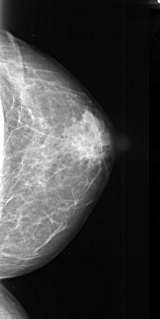

A_1022_1.LEFT_MLO

LEFT_MLO LINES 4756 PIXELS_PER_LINE 2476 BITS_PER_PIXEL 16 RESOLUTION 42 OVERLAY